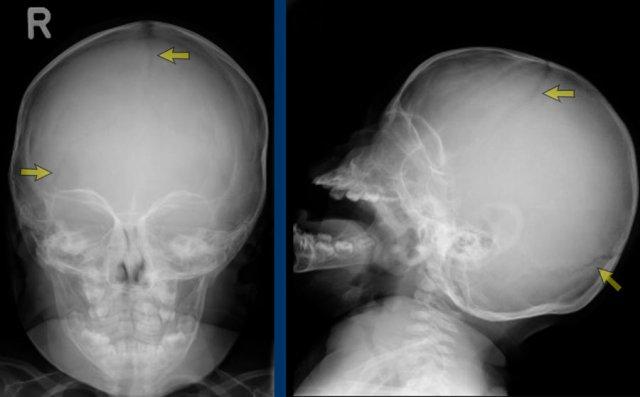

X-quang sọ cho thấy các đường khớp còn mở.

Cần lưu ý rằng X-quang có giá trị hạn chế trong việc đánh giá đường khớp dọc giữa, và tình trạng đóng khớp một phần của đường khớp này có thể bị bỏ sót.